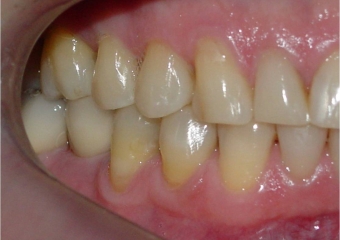

Mordida após a remoção do aparelho